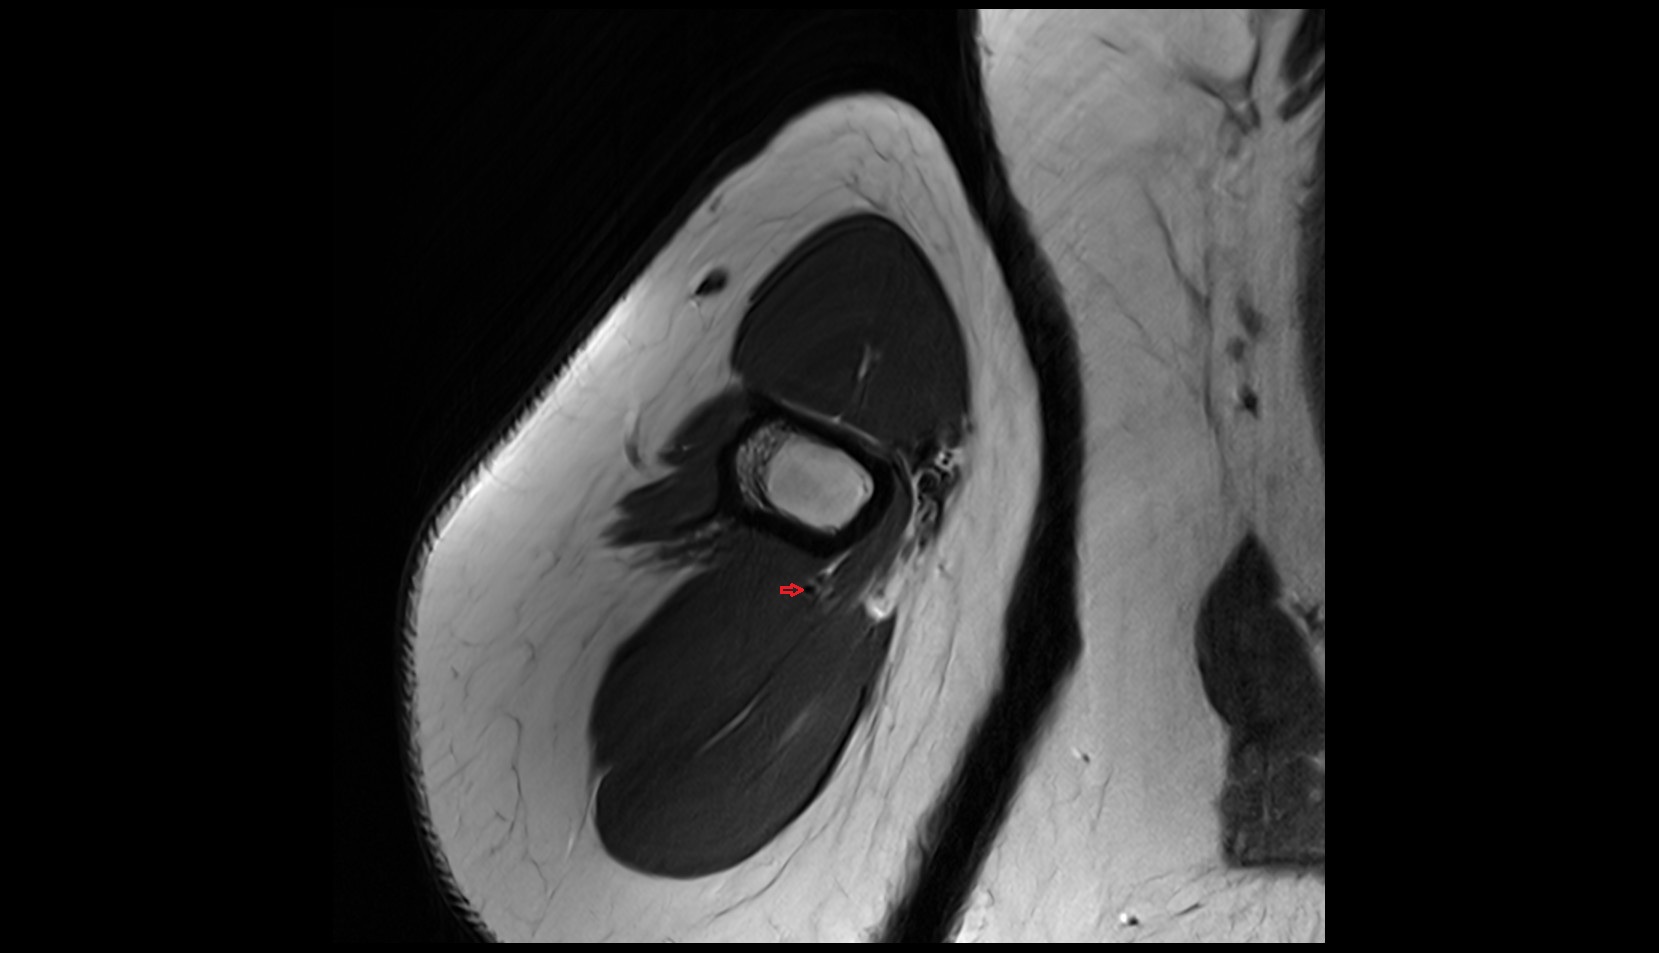

- Knee Joint